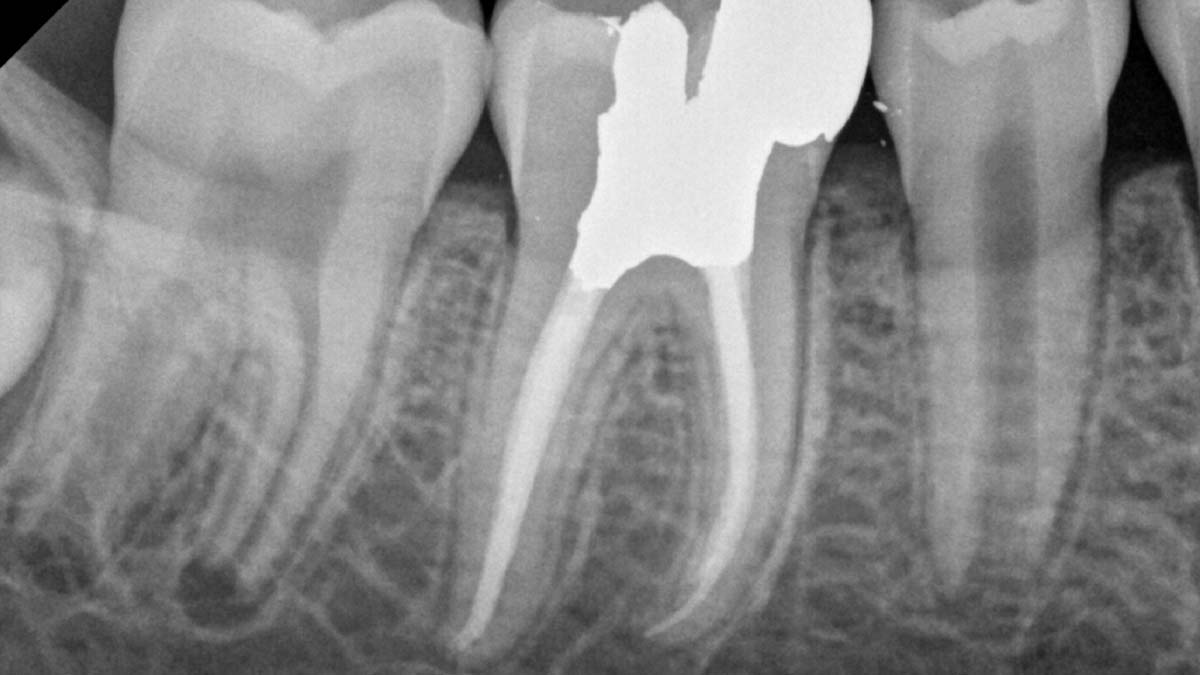

À droite : Gutta-Smart et Conform Fit utilisent la même gutta-percha avancée pour une cohérence radiographique.

Avec l’aimable autorisation du Dr Nathaniel Behrents, Fayetteville, AR